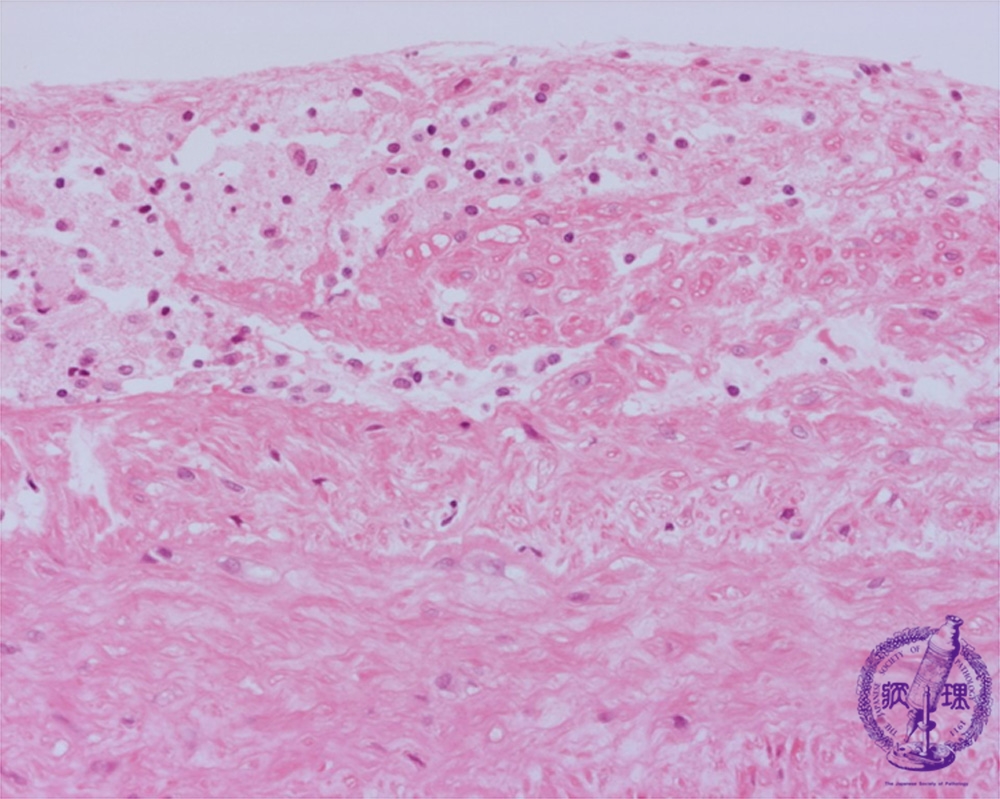

- ★(9)Atheroslerosis (aortic atherosclerosis) li>

Microscopic image (HE, high power view): Sub-endothelial lipid accumulation within foamy (lipid laden) macrophages (blue circles). The elastic lamellae of the tunica media is partially effaced (red line).